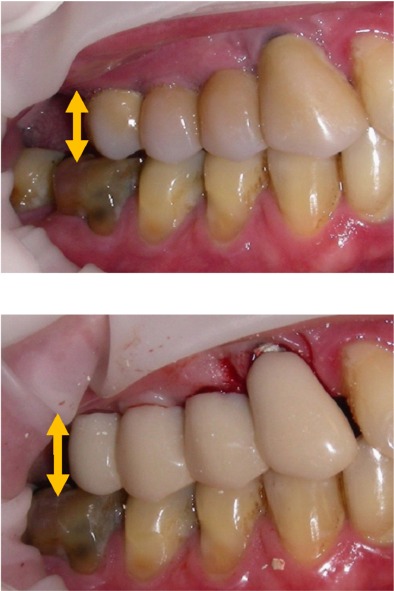

È stato selezionato un paziente che richiedeva una riabilitazione del I quadrante mediante protesi fissa ad ancoraggio implantare. Gli impianti sono stati posizionati in sede 1.3, 1.4, 1.5 e la truttura protesica predisposta per sopportare un elemento in estensione in sede distale. Lo studio funzionale dell’apparato masticatorio è stato eseguito con EMG di superficie dei muscoli masticatori (k7 Evaluation System, Myotronics) valutando il lavoro muscolare in massima contrazione volontaria (MVC) del muscolo massetere (RMM) e del muscolo temporale (RTA) omolaterali e studiando il differente tempo di attivazione di tutti i muscoli elevatori della mandibola nel percorso dalla posizione di riposo a quella di massima intercuspidazione. La posizione della mandibola è stata registrata 1) registrando con materiale siliconico la dimensione verticale indicata dal paziente con movimento volontario fino al massimo contatto dentale e 2) dopo stimolazione trigeminale TENS mantenuta per 45 minuti per rilassare la muscolatura e deprogrammare il sistema propriocettivo dell’apparato stomatognatico.Dalle due registrazioni sono state costruite due differenti protesi provvisorie che sono studiate nel rendimento neuromuscolare.